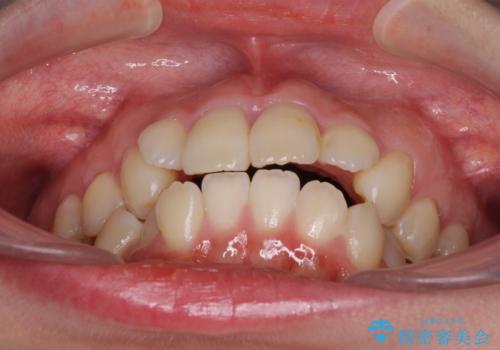

診断の結果、上顎左右第一小臼歯4本抜歯により、叢生を解消するとともに口元を引っ込めていくことが望ましいと判断しました。

抜歯矯正による口元の改善にはワイヤー矯正が望ましいのですが、ダンサーとしての仕事を行っているため、インビザラインにて治療を行うこととしました。